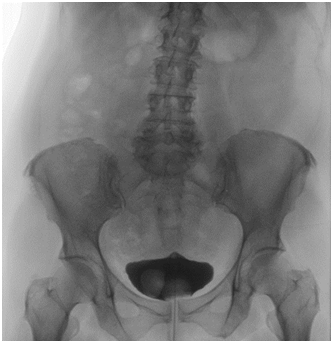

54-year-old female presents to the emergency department with complaint of obstructive voiding, urine leakage, and pelvic pain within troital bulge. She denies any prior irritative voiding symptoms, recurrent urinary tract infections, flank pain or gross hematuria. On physical exam she was found to have a 3x2.5cm mass protruding from her urethra with active urine leakage from her ureteric orifice (Figure 1). Manual reduction was attempted at bedside, but was not pursued because of pain. Previously, the patient was evaluated with CT scan for microscopic hematuria, which showed a ureterocele with associated megaureter (Figure 2). Further evaluation with a voiding cystourethrogram did not reveal reflux and cystoscopy confirmed a single ureterocele without any other bladder masses (Figure 3). During this acute event of urinary retention, the patient stated that shep referred minimally invasive management, and she was taken urgently to the OR for reduction of her ureterocele under anesthesia. Again, manual reduction was attempted, however was unable to be performed. A 22 french rigid cystoscopy was then utilized with constant, even pressure to reduce the ureterocele. After complete reduction, cystoscopy was performed demonstrating bilateral brisk efflux and a 16 french catheter was placed with return of clear yellow urine. She was discharged to home later that day with the catheter in placed. It was subsequently removed a week later and the she was able to void with a post void residual less than 50ml. Follow up nuclear medicine functional study was performed that showed preserved renal function without evidence of obstruction. She has since been asymptomatic since reduction.

Figure 1 Gross picture of ureterocele prolapse.